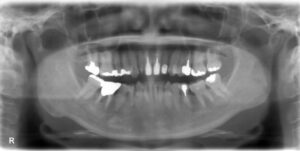

• 上下顎オールオン6症例

BEFORE AFTER 63歳男性/上顎6本・下顎6本 【治療内容】 全体的に歯が揺れてお食事がとりづらくなり、来院さ…